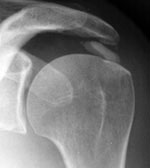

- La capsulite rétractile, à condition que l’injection soit vraiment faite dans l’articulation. Au besoin cette injection sera faite sous contrôle radiologique pour être sûr que l’aiguille se situe bien dans l’articulation.